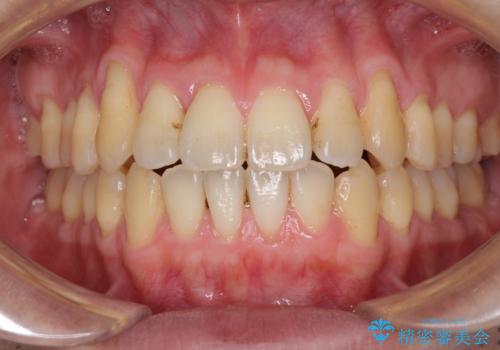

- 上下の前歯の反対咬合を気にして来院された患者様です。

インビザラインを用い、下顎はIPR(歯と歯の間を削る)と歯列全体を後方に移動させ、上顎は前歯を持ち上げることで、反対咬合を改善していくこととしました。

八重歯の歯根が見えている点も気になっているので、矯正歯科治療後に歯肉移植による根面被覆を行うこととしました。

矯正治療により元々気になっていた八重歯と、反対咬合が改善された歯の2本に対して根面被覆を行い、審美面の改善も達成しました。